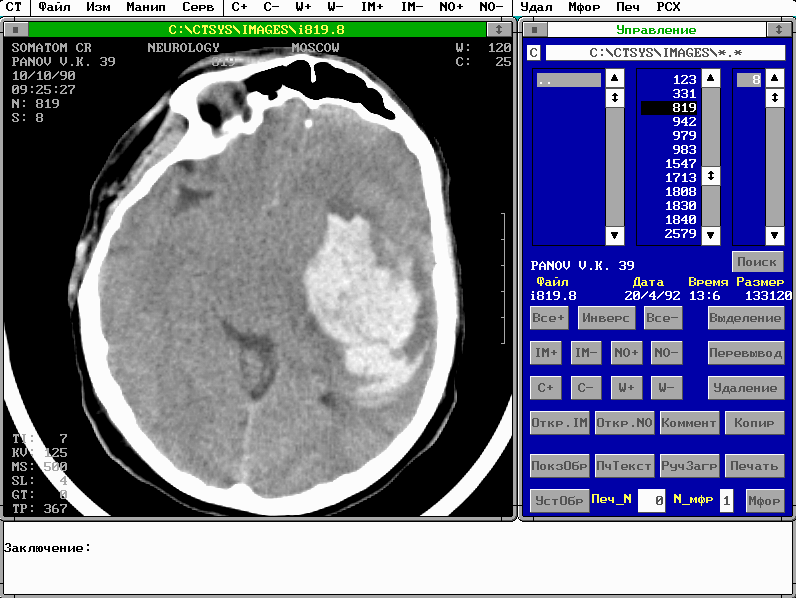

Как войти в систему. После инсталляции системы, проводимой разработчиками, она находится в рабочем директории c:\ctsys\exe. Надо войти в него и выполнить команду ct_work.bat. На экране дисплея появится нечто, похожее на нижеприведенную иллюстрацию:

Это конфигурация для работы с изображениями. На рисунке видны два главных окна системы: окно Управление (справа) и окно Изображения, с изображением среза, полученного на рентгеновском томографе. Как выйти из системы. Первый вариант: надо активизировать в верхнем меню элемент CT, появится вертикальное подменю, и щелкнуть мышью на элементе Выход. Второй вариант: в латинском нижнем режиме клавиатуры (для активизации латинского регистра надо одновременно нажать клавиши Control-Shift, для активизации русского регистра - клавиши Alt-Shift - зеленая рамка по периметру экрана - признак русского регистра) нажмите клавишу x. После выполненных действий в любом варианте появится окно подтверждения выхода. Если вы не передумали выйти из системы щелкните мышью на кнопке Да окна подтверждения или при работе с клавиатуры: переведите курсор на кнопку Да и нажмите клавишу Enter. ГЛАВА 1. Работа с изображениями. Какие окна выведены на экран после входа в систему. Это окна конфигурации для работы с изображениями. Они перечислены ниже. Первые три окна присутствуют всегда.. Четвертое окно FG-сервис выводится, если в вашей системе есть оборудование для ввода видеосигнала